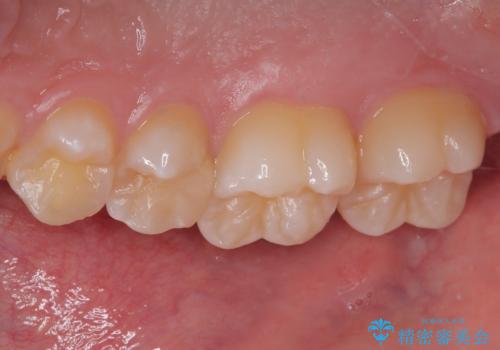

歯間部の自分では気づきにくい虫歯 セラミックインレー修復

- 定期健診で歯間部の齲蝕が見つかった患者様です。

食べ物が頻繁に詰まるとのことで、レントゲンで確認したところ、歯間部に齲蝕が認められました。

このまま放置すると齲蝕が進行し、歯の神経まで及んでしまう危険性があるため、精度の高いセラミックインレー修復を行いました。

ぱっと見ではわかりずらい齲蝕ですが、レントゲン写真でははっきりと確認することができます。